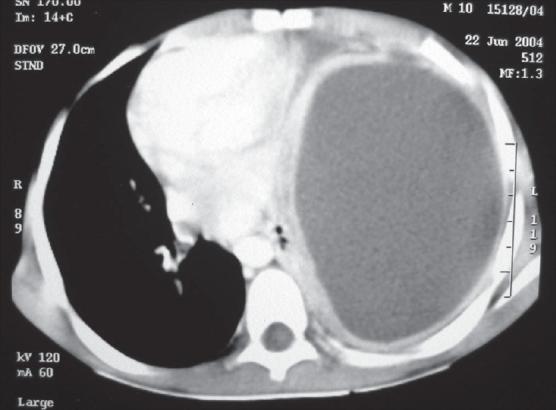

小儿脓胸:手术治疗

Empyema thoracis can produce significant morbidity in children if inadequately treated. Correct evaluation of the stage of the disease, the clinical condition of the child and proper assessment of the response to conservative treatment is crucial in deciding the mode of further surgical intervention. This ranges from intercostal chest tube drainage and video-assisted thoracoscopic surgery to open decortication. Surgical decortication becomes mandatory in neglected cases; it gives very gratifying results ameliorating the disease rapidly and is well tolerated by young patients. This article reviews the current literature and discusses the important considerations while managing these patients. Indications for surgery are highlighted, based on our large experience at a tertiary care center.

如果治疗不当,小儿脓胸可导致严重的发病情况。正确评估疾病阶段、患儿临床状况以及对保守治疗反应的恰当评估,对于决定进一步手术干预方式至关重要。这包括肋间胸腔闭式引流、电视辅助胸腔镜手术以及开胸纤维板剥脱术。在被忽视的病例中,手术纤维板剥脱术成为必要手段;它能迅速改善病情,取得非常令人满意的效果,且年轻患者耐受性良好。本文回顾了当前文献,并讨论了管理这些患者时的重要注意事项。基于我们在三级医疗中心的丰富经验,突出了手术适应症。